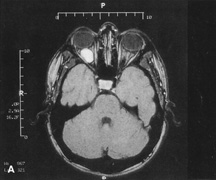

always can be extended farther posteriorly if exposure is inadequate.   Figure 10. A. Large, well-encapsulated intraconal mass on MR scan. B. Small lateral canthotomy incision will be used to perform lateral orbitotomy

and remove the intraconal mass.

Figure 10. A. Large, well-encapsulated intraconal mass on MR scan. B. Small lateral canthotomy incision will be used to perform lateral orbitotomy

and remove the intraconal mass.